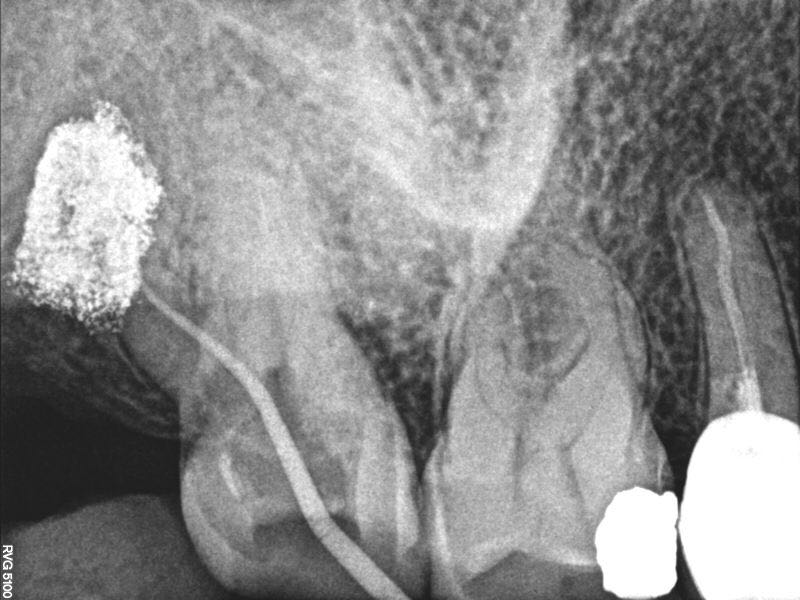

插针片可见远颊根s型弯曲